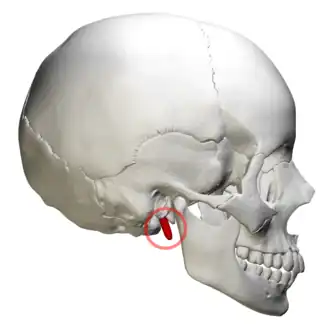

Right side of the skull. Styloid process shown in red | |

The temporal styloid process is a slender bony process of the temporal bone extending downward and forward from the undersurface of the temporal bone[1] just below the ear. The styloid process gives attachments to several muscles, and ligaments.

The styloid process is a slender and pointed bony process of the temporal bone projecting anteroinferiorly from the inferior surface of the temporal bone[1] just below the ear. Its length normally ranges from just under 3 cm to just over 4 cm. It is usually nearly straight, but may be curved in some individuals.[1]